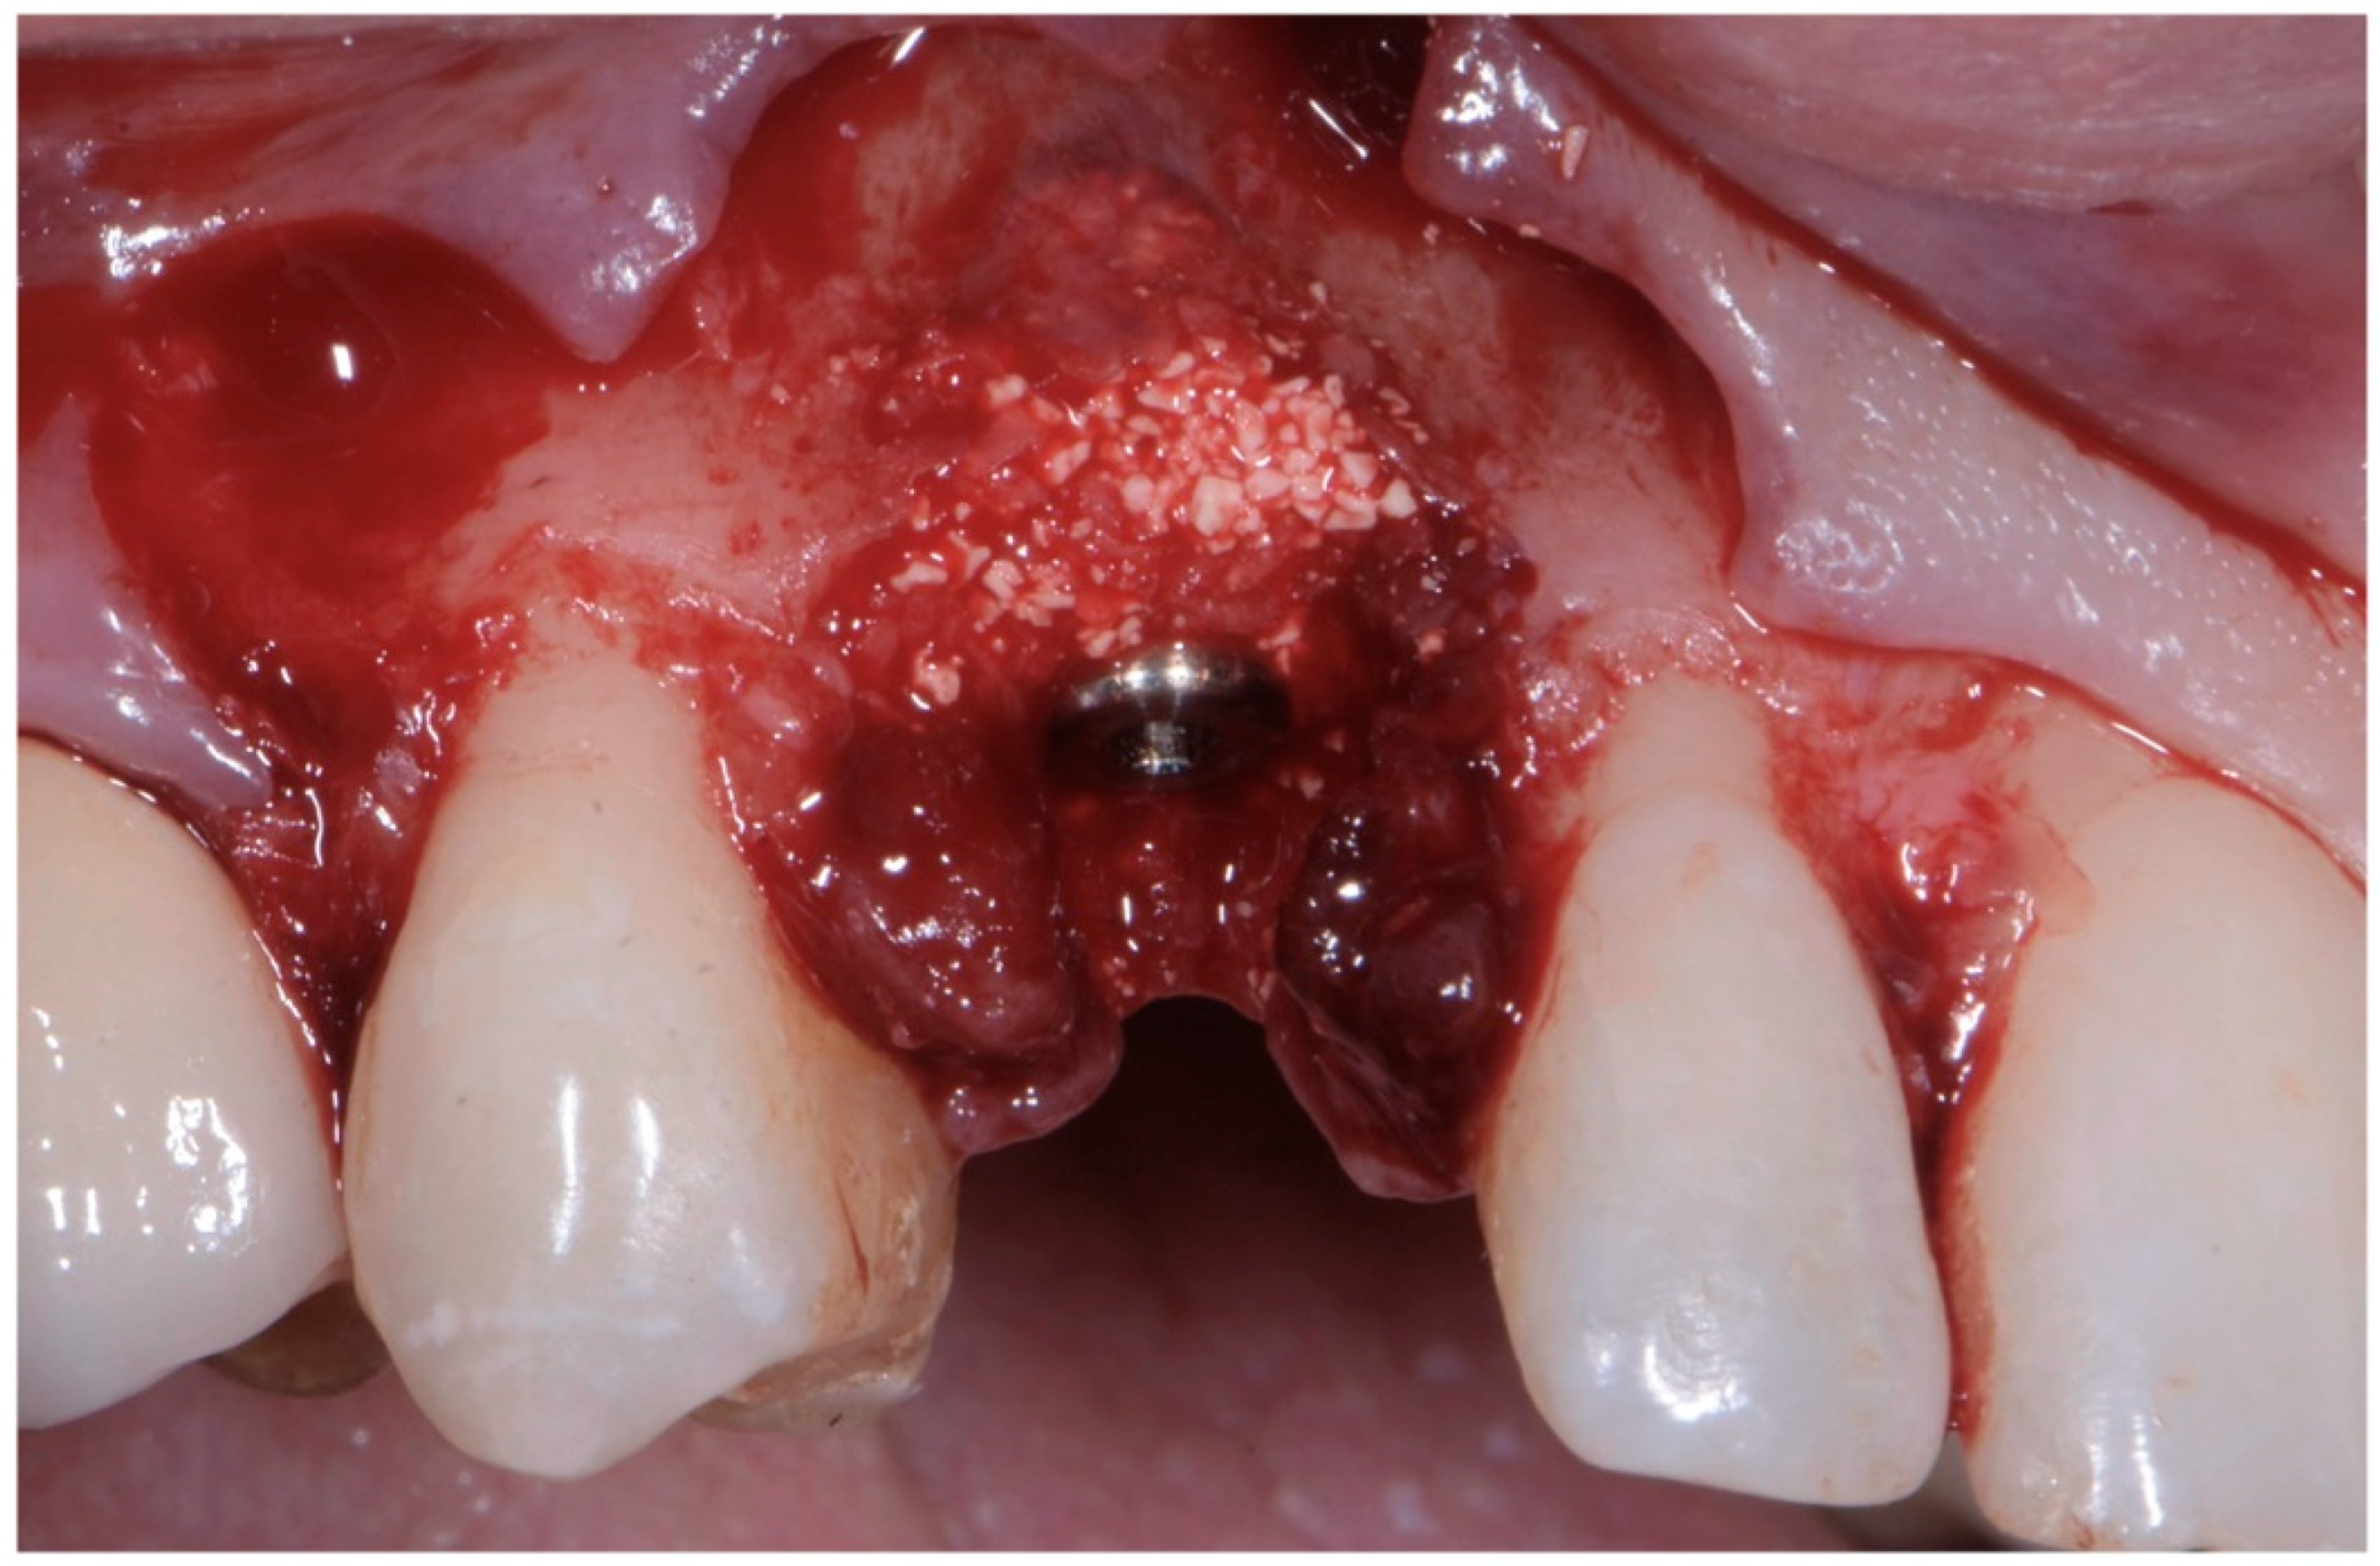

The implant site was prepared in a fully guided manner, using drills of progressively larger diameter, so that at the moment of guided implant insertion, the fixture could reach the pre-established position with enough primary stability to consent immediate provisionalization (35 Ncm) (Figure 6a,b). The implant shoulder should be palatal with respect to the imaginary line that connects the buccal profile of the adjacent teeth without placing it so that it is excessively palatal, in order to avoid creating prosthetic emergence profiles that are too horizontal, which are difficult to maintain in terms of hygiene.

As already evaluated during software planning, after implant insertion, a buccal bone dehiscence of 2 mm occurred. The remaining buccal bone thickness was less than 1 mm. A mixture of biomaterial (Cerabone; Botiss) and autologous bone was placed to cover the exposed implant threads and the thin layer of remaining buccal bone and to fill the gap between the implant surface and the socket wall (Figure 7). Bone filler material should be limited to the rough implant surface, extending as little as possible to the transmucosal collar; however, the biomaterial positioning should be slightly in excess to avoid the loss of biomaterial during the following phase. If there is still an excess, it should be removed just before the very last suture. The biomaterial was then stabilized using a thin pericardium membrane (Jason Membrane; Botiss) placed between the bone particles and a connective-tissue graft (Figure 8a,b). The pericardium membrane was sutured to the periosteum left appositively laterally to the membrane.

Figure 6. (a,b) Implant placement after guided preparation of implant site.

Figure 7. Biomaterial and autologous bone placed to cover the exposed implant threads and to fill the gap between implant surface and socket wall.